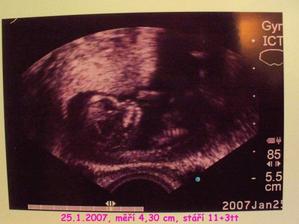

SRPŇÁTKA 2007 - fotky UTZ

album věnované mimískům, které se narodí v srpnu 2007 a jejich maminkám ze "Společného termínu SRPEN"